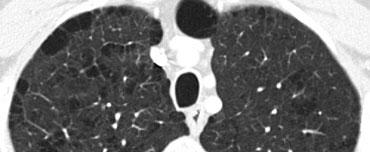

Ca lâm sàng minh họa: Ung thư lan tràn theo đường bạch huyết

Hình ảnh

Dày vách khu trú, không đều ở thùy trên phổi phải trên bệnh nhân có tiền sử ác tính đã biết. Dấu hiệu này điển hình cho ung thư phổi lan tràn theo đường bạch huyết.

Các đặc điểm hỗ trợ chẩn đoán bao gồm:

- Hạch bạch huyết trung thất

- Tổn thương dạng nốt ở phổi trái, nhiều khả năng là di căn.

Ung thư phổi lan tràn theo đường bạch huyết (PLC):

- Trong 50% trường hợp, dày vách có tính chất khu trú hoặc một bên, giúp phân biệt với các nguyên nhân khác (ví dụ: sarcoidosis, phù phổi do tim).

- Hạch bạch huyết rốn phổi có thể thấy trong 50% bệnh nhân, và thường có tiền sử bệnh ác tính.